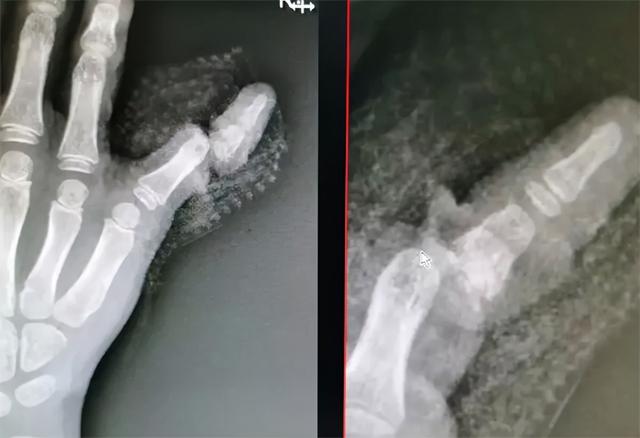

谁也没想过,一阵大风吹来,阳台门“砰”的一声关上,女儿佳佳的小拇指被门框夹个正着。

妈妈赶紧跑过去,眼前的情景简直让她不敢看。